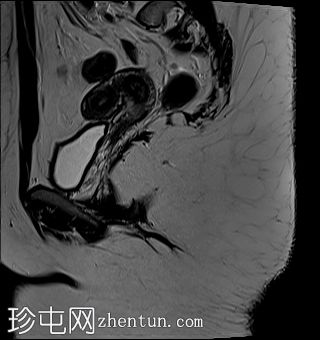

矢状位

T2加权像

子宫外底轮廓清晰,肌层较厚,将子宫内膜腔分隔成两个腔,纤维层较薄,向下延伸至宫颈外口。子宫内膜厚度正常,两个子宫腔交界区清晰,未见明显的实性局灶性病变。

本病例展示了典型的纵隔子宫影像学表现:增厚的肌层隔膜将子宫内膜腔分隔成两个腔,并有一层薄的纤维隔膜延伸至子宫颈外口水平,符合完全纵隔子宫的特征。

隔膜可能由纤维组织(T2信号低)、肌层组织(中等信号)或两者共同构成,如本病例所示。